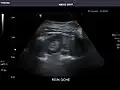

Spleen -